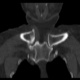

Женщина за 50 лет. Жалобы на припухлость и болезненость в области правого грудинно-ключичного сочленения. Принял решение не проводить рентгенографию, а сразу направить на КТ.

Хорошо. Тогда - мнение врача КТ, с коим я абсолютно согласен, - асептический некроз грудинного конца ключицы.

Не против того, что в какой то мере здесь присутствуют и явления артрозо-артрита, но ТАКИЕ изменения структуры грудинного конца ключицы, да еще и с наличием секвестров, вряд ли были бы характерны только для артроза.

1.Клинически при осмотре - припухлость, болезненная, без особых наружных признаков воспаления, существующая несколько месяцев, медленно прогрессирующая в размерах, ограничение движения в плече (из за болезненности в ключично-грудинном сочленении).

Не вижу явных признаков некроза, а вот изменения суставной поверхности в виде изьеденности по ключице и грудине пристутствуют. Единственное минус - нет расширения суставной щели. То, что принимаете за секвестры, скорее всего, являются изменениями края кости за счёт воспаления окружающих тканей: ревматоидный артрит (к примеру). В таких случаях проверяю себя УЗИ (изменения мягких тканей).

1. Если бы не вовлечённость значительной части ключицы (кости), тоже бы заключил артрозо-артрит.

2. Я не врач КТ, но. имея некоторый рентгенологический и клинический опыт прихожу к выводу. что сия ситуация выходит за рамки артрозо-артрита, а первое мнение было именно врача КТ - об асептическом некрозе.

4. Меня, в первую очередь, смущает тоже большой обьем поражения кости, что не характерно для артроза.

Вижу подобную картину не так уж и редко и трактую это как артроз-артрит. Причем, вижу это в ста процентах случаев как случайную находку (пациенты с ДТП и прочие травматики) и без всякой клиники в анамнезе. Убедительных данных (признаков) за ас.некроз тут не вижу. У меня нет наработок, какие изменения происходят в итоге в костях суставов при зазличных видах артритов. Вероятно, что разница может быть очень серьезная.

Ладно, предположим. Асептический некроз. Но сейчас-то мы видим явную дегенератику + склеротическое уплотнение + клиника. Чем не банальные артрозоартритные дела с морфологической декомпенсацией? Или мы говорим об исходе асептического некроза?